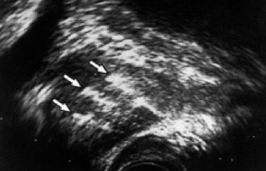

Next was a "biopsy". This  is not nice as tiny hollow needles, guided by

ultrasonic pictures, collect samples through the prostate (via the back passage wall).